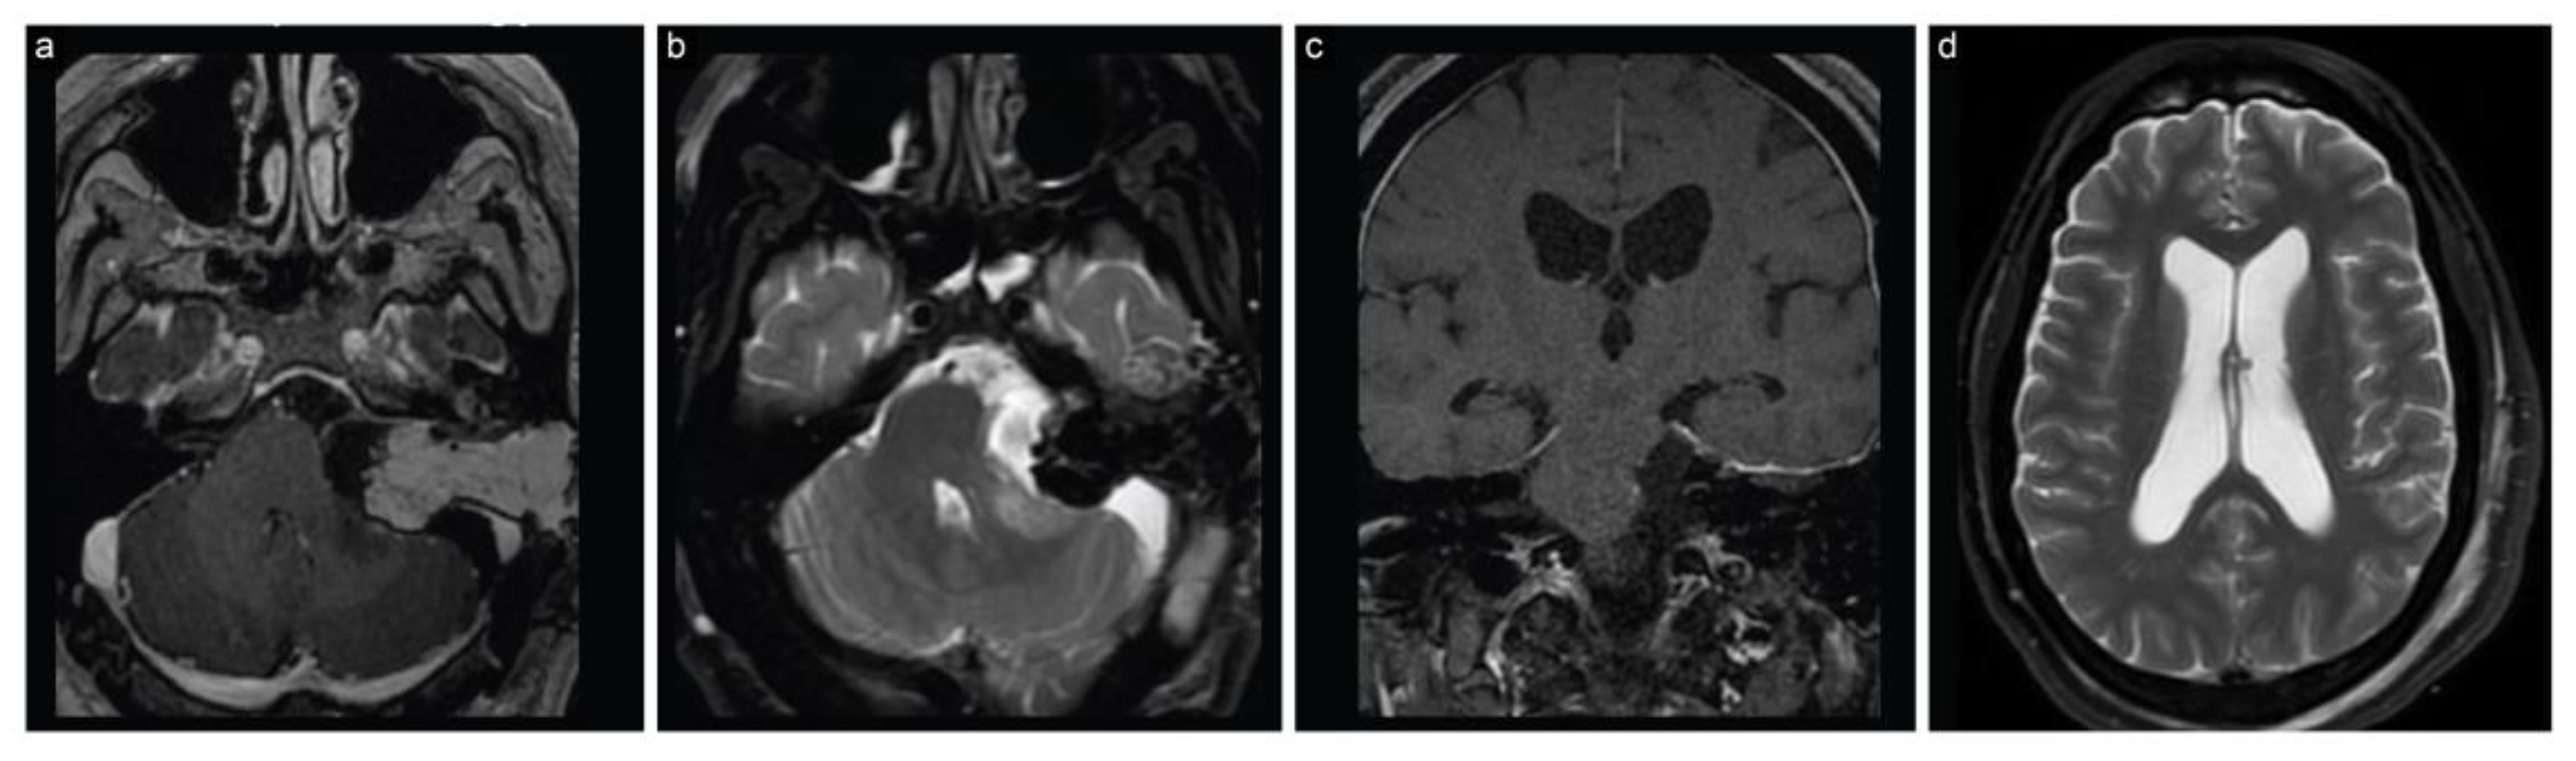

The second case is a 48-year-old man who had presented with dizziness and numbness on the left side of his face for the past six weeks. These symptoms had been escalating, and were accompanied by a severe, newly developed headache. An MRI scan revealed a large cystic left cerebellopontine angle lesion (4.1 cm × 2.5 cm × 2.8 cm), suggestive of a VS, along with signs of recent hemorrhage within the lesion (Figure 4). An initial audiogram revealed moderate to severe sensorineural hearing loss, with no serviceable hearing on the left side.

Figure 4.

Case 2 preoperative neuroimaging. (a) Axial T1-weighted postcontrast, (b) axial T2-weighted, (c) coronal T1-weighted postcontrast, and (d) coronal T2 FLAIR MRI scans show a large cystic CPA lesion, suggesting a vestibular schwannoma along with recent intratumoral hemorrhage.